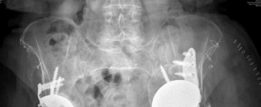

4. Bone Grafting:

To address the extensive bone loss and facilitate long-term biological reconstruction, a combination of structural and morselized allograft was employed.

* Structural Allograft: A large femoral head allograft was shaped to fill the large superior segmental defect, providing initial structural support and helping to reconstitute the superior dome. This graft was initially held in place with temporary K-wires.

* Morselized Cancellous Allograft: Mixed with bone marrow aspirate (BMA) from the greater trochanter, this cancellous graft was packed tightly into all remaining cavitary defects to promote osteoconduction and eventual incorporation.

![Image](/media/upload/57ce8fa4-877c-48cf-b9af-9c7c79d0f919.png)

This image depicts a stage of the surgery where the defect has been debrided, and possibly initial bone grafting or reaming is underway, showing the exposed bone deficiency.